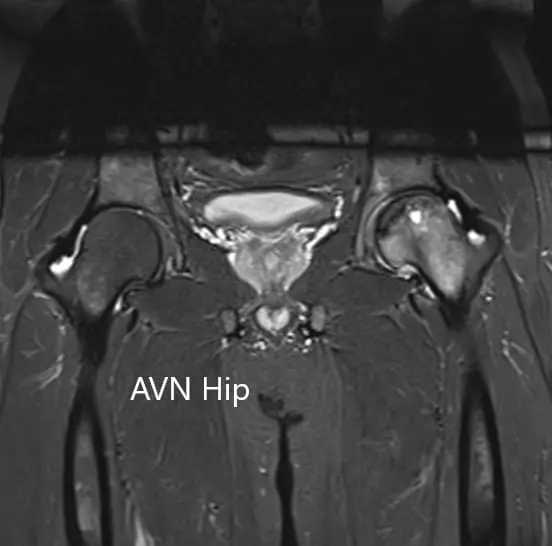

An MRI was obtained which suggested avascular necrosis of the left hip stage 3. There were altered signal intensity and bone marrow edema.

T2WI coronal section of MRI showing AVN hip.